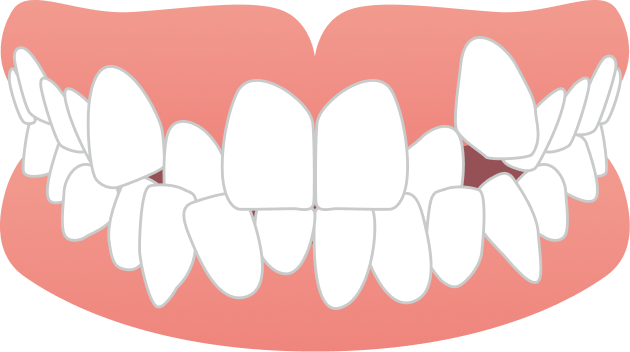

20代女性 前歯のガタガタが気になる

こちらの症例は20代女性の患者さまで、「下の前歯が1本前に出ていること」や「右上の前歯が出て見えること」を気にされて来院されました。

BEFORE